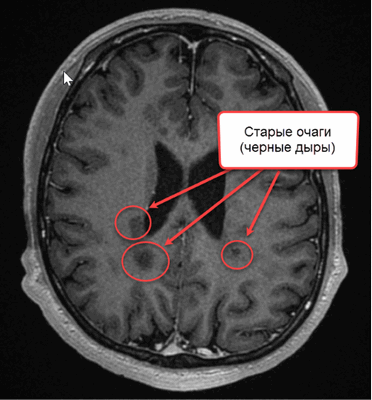

Конечным этапом прогрессирования поражения при рассеянном склерозе являются “черные дыры”, свидетельствующие о деструкции аксонов.

![очаги рассеянного склероза на МРТ]()

На МР-томограмме головного мозга в Т1 ВИ можно увидеть многолетние очаги РС (обозначены стрелками)